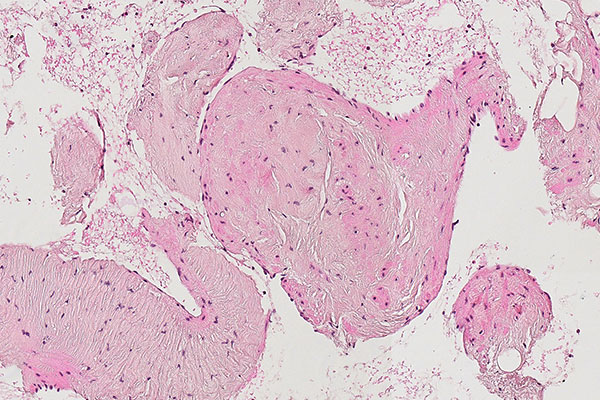

Histopathologischer Schnitt; Hämatoxylin-Eosin-Färbung (HE), 90-fache Vergrößerung des Stanzzylinders. Stanzzylinder mit Anteilen der venösen Malformation mit dicht gelagerten, irregulär konfigurierten, großkalibrigen venösen Gefäßanschnitten. Diese erscheinen nicht tubulär, wie bei einem normalen Gefäßanschnitt, sondern wie „umgestülpt“. Das Lumen ist solide und das Blut überall außenherum.

Die venöse Malformation ist schwammartig blutgefüllt ohne echte solide Anteile, ähnlich einem Schweizer Käse mit viel Luft (Luftlöcher = blutgefüllte Hohlräume; Käse = dysplastische, venenartige Wandstrukturen). Die eigentlichen dysplastischen Venenwände machen also in der blutgefüllten Gesamtläsion nur einen Bruchteil des Volumens aus und erscheinen meist nicht rohrförmig wie ein Gefäß, sondern fuchsbauartig irregulär verzweigt.